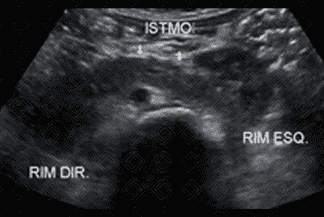

Texto alternativo para a imagem Figuras 1, 2, 3 e 4. Créditos: Dra. Elazir Mota - Rio de Janeiro/RJ

Descrição das figuras 1, 2, 3 e 4: Ultrassonografia das vias urinárias evidenciando rins em ferradura. Observe que o rim esquerdo é menor e apresenta alteração rotacional. Ao avaliar a linha média, anteriormente à aorta, observa-se a fusão dos polos renais inferiores.

• Ultrassonografia das vias urinárias: N ota-se fusão dos pólos inferiores dos rins na linha média, anteriormente à aorta (como nas imagens radiológicas). Sempre avaliar bexiga e sistema coletor, buscando por sinais de dilatação, já que nestes casos é comum a dificuldade de drenagem nas pelves renais;